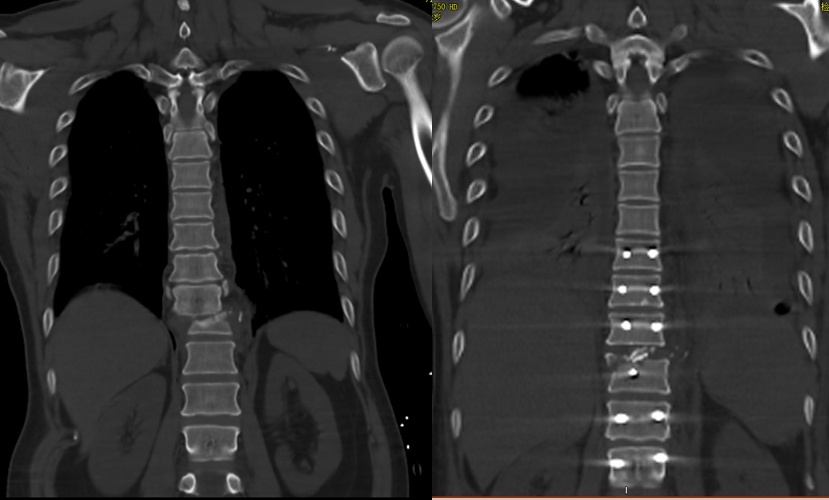

据介绍,此次手术采用了复位固定融合术,具体包括胸椎骨折脱位切开复位椎弓根钉棒内固定术、胸椎植骨术和椎骨减压术。在胸椎植骨术中,医生取患者自身的碎裂脊柱骨附件,植入到其脊柱脱位椎骨间,以起到支撑作用。林伟鹏解释,“这部分植骨将逐渐与患者的脊柱融合,有助于脊柱恢复。”

令人欣慰的是,手术过程中患者并未出现大出血等意外情况,整体进展顺利。术后,患者被送入重症监护室进行密切监测,情况稳定后已转回骨科病房。近期CT检查显示,患者的脊柱已实现良好复位。

治疗前后对比图。